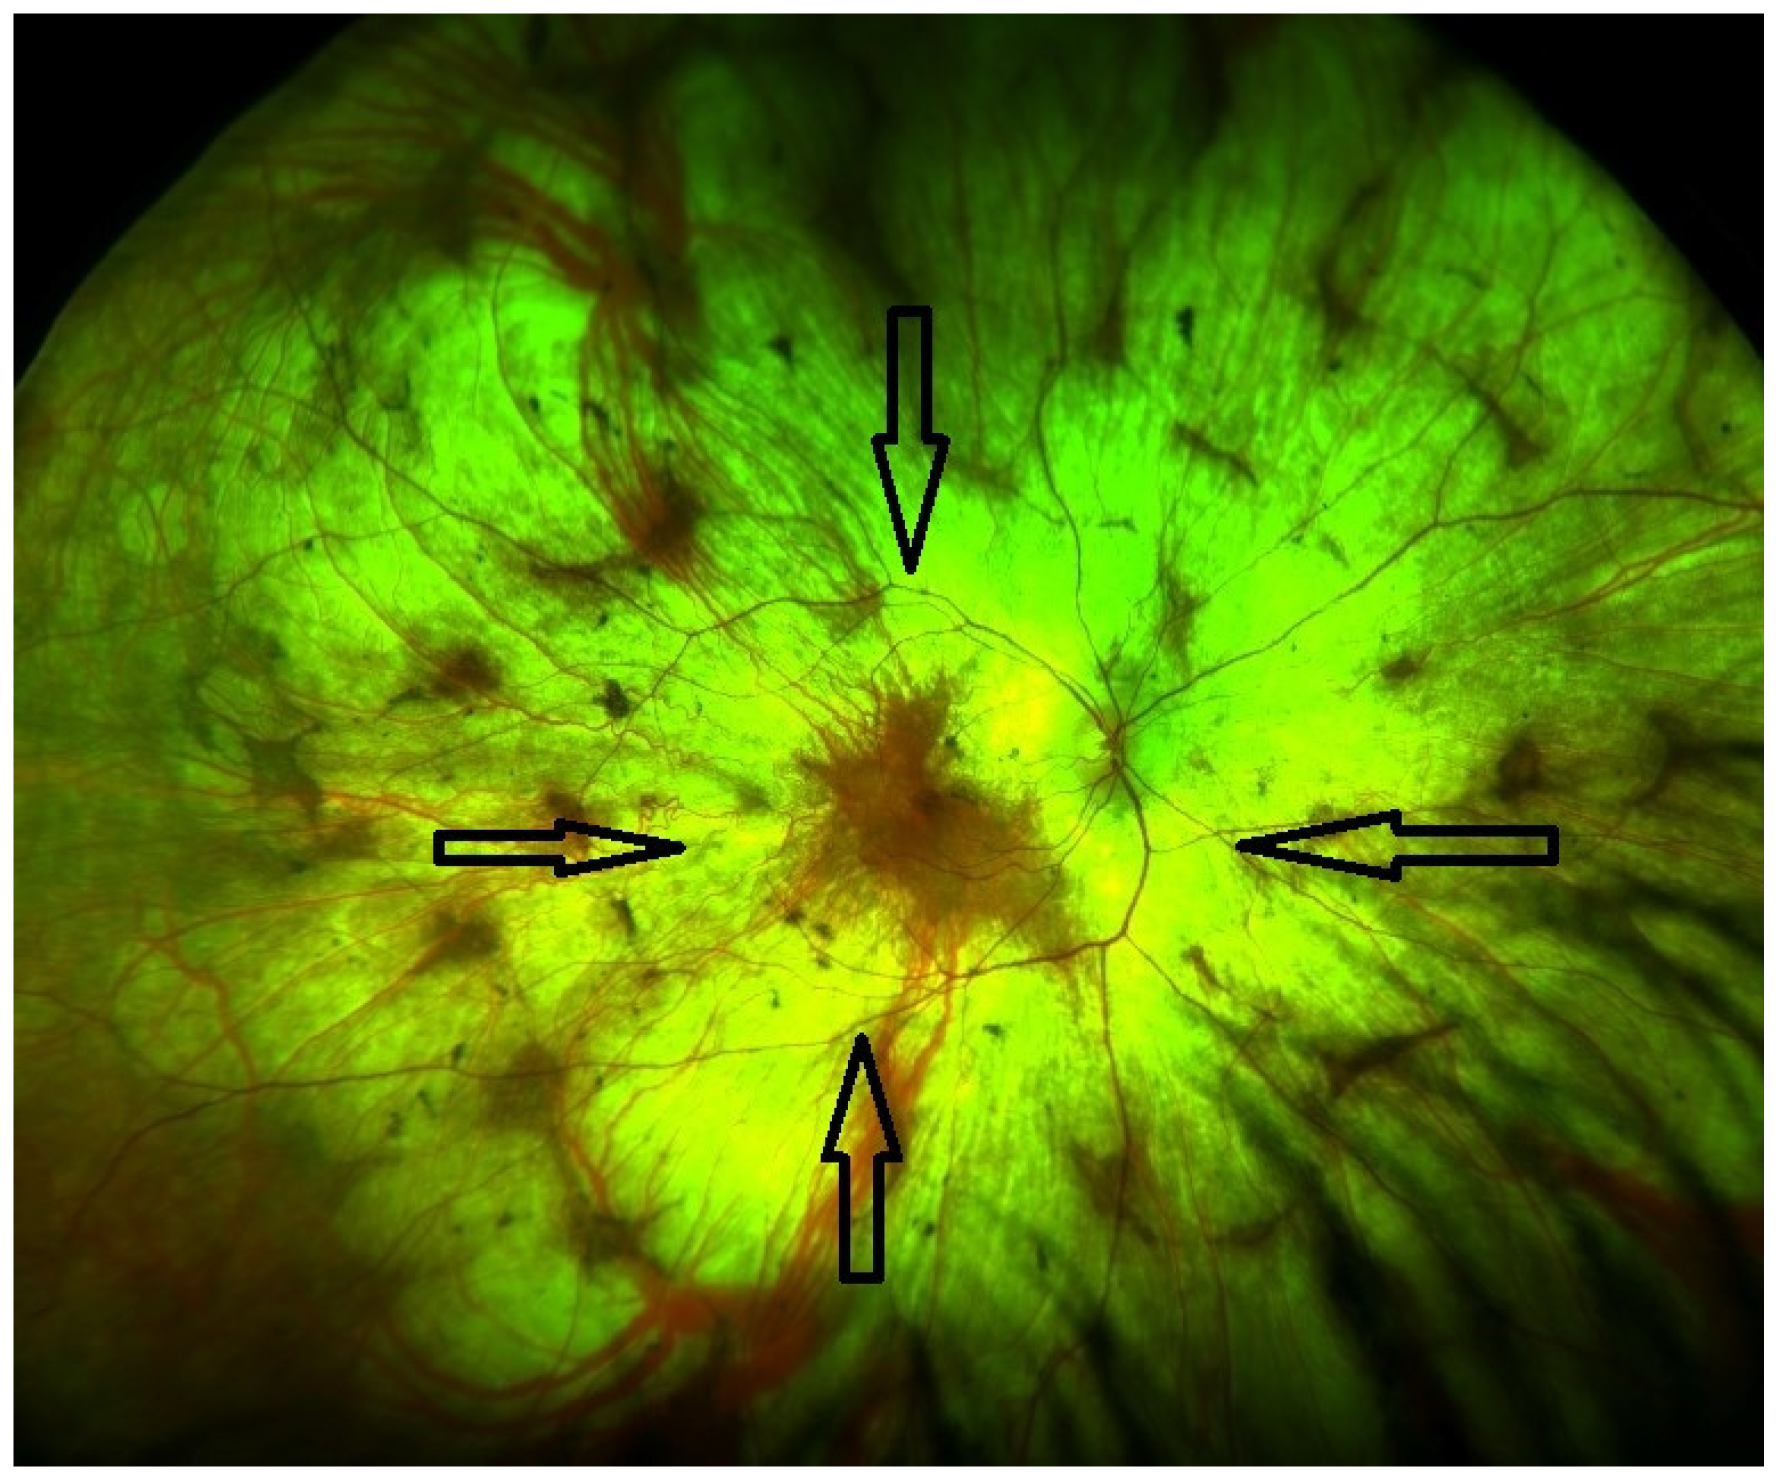

| Late stage | Defined by the encroachment of scotomas and/or reduced sensitivity well within the vascular arcades and encroaching the central region (Figure 1 and Figure 2). | - Full field perimetry (static or kinetic) - Mesopic microperimetry - Patient-reported outcomes - OCT (Figure 3) - FAF - FST - BCVA/LLVA |